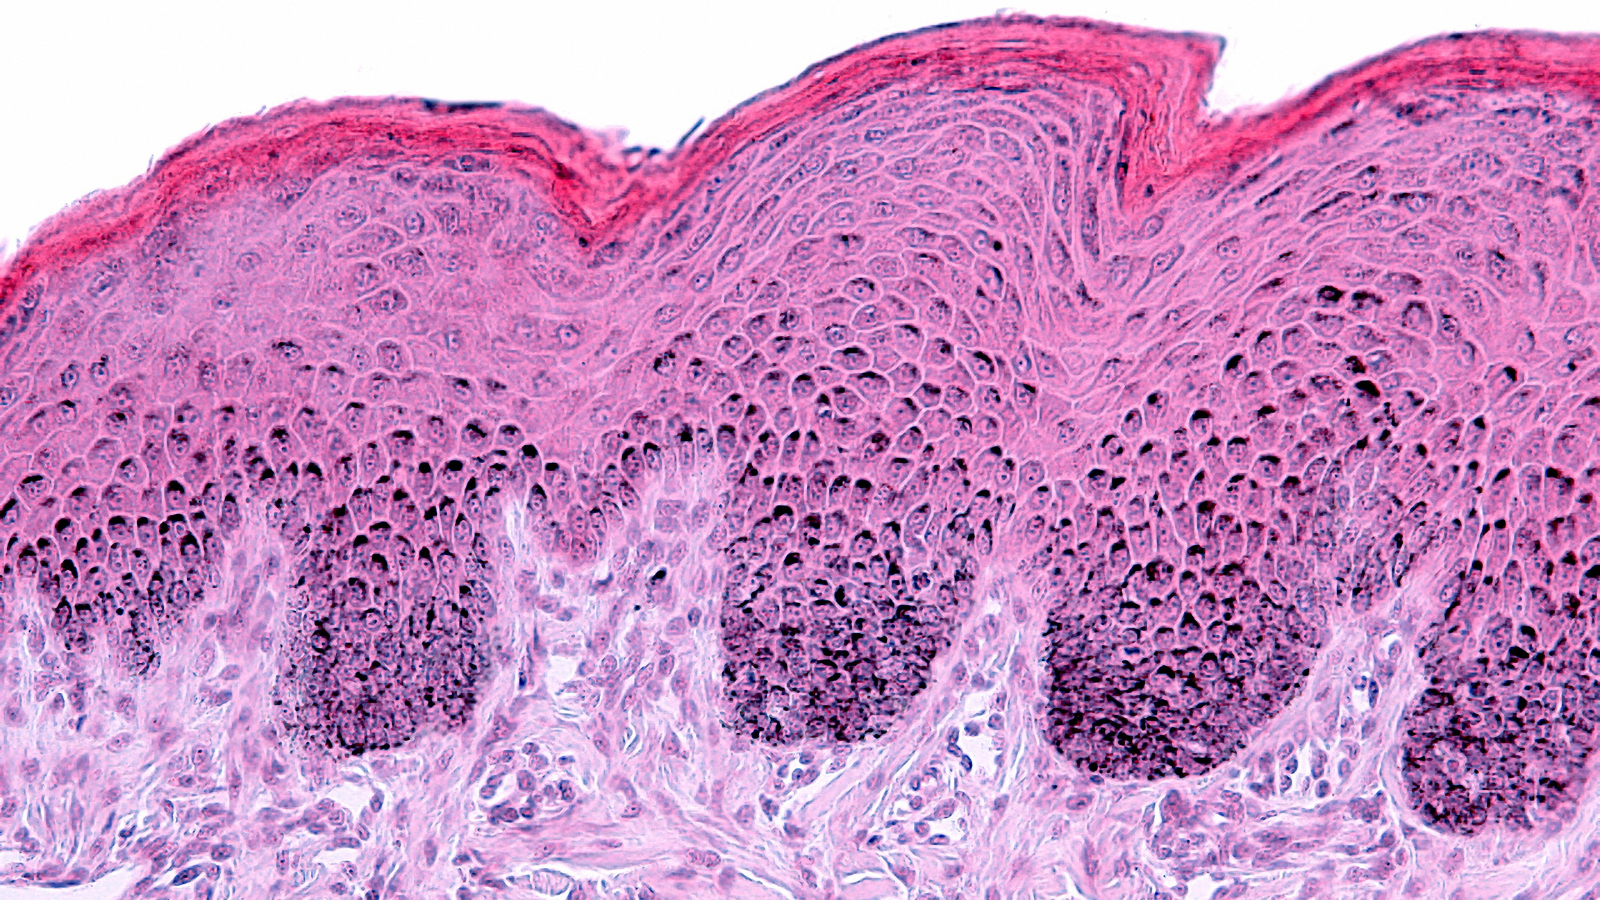

• Microbiological analyses: hygiene control, conservation tests